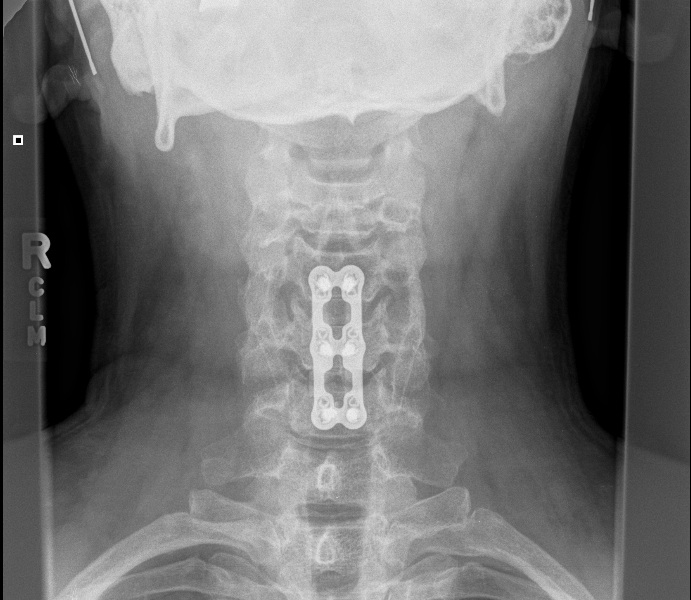

Saw my surgeon today with fresh X-rays. (below)

He likes how it is looking, wants to see me again in three months, at which time we'll discuss my return to flying. Thus grounded for the summer, I'll have to miss Hyner this weekend and July 4th.

Wow, Cragin, those are some impressive x-rays. Hope you can make it out to Hyner for Labor Day.

Getting just a wee bit intimate, are we Cragin?

Naw, how can anything from the neck up be that intimate?brianvh wrote:Getting just a wee bit intimate, are we Cragin?

Well, I guess I have given proof positive that I've been permanently screwed.

Neck up?! That first picture had me thinking I was looking at lower back and thigh...I'm not titillated anymore at all!